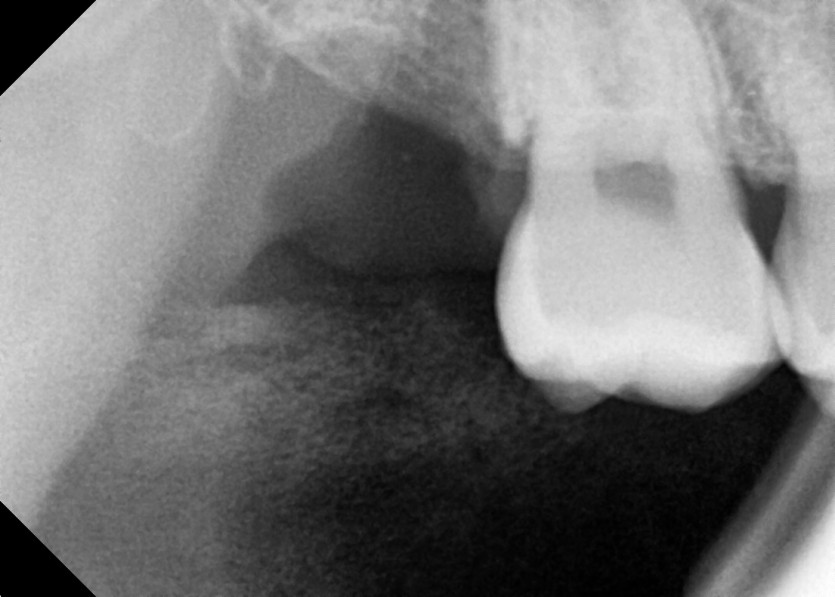

#18,48 사랑니 발치

구강 외과 전문의가 당일 발치했습니다.